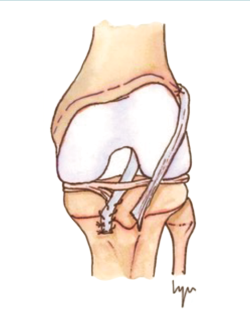

Las técnicas de “ahorro fisario” o physeal sparing

Figura 3. Técnica de la banda iliotibial.

Estas técnicas evitan la agresión de la placa fisaria. Una de las primeras fue descrita por MacIntosh y Darby(11), y modificada posteriormente por Micheli(68), conocida como la técnica de la “cintilla iliotibial” (illiotibial band –ITB–). Utiliza parte de la cintilla iliotibial como autoinjerto, dejando su porción distal unida al tubérculo de Gerdy. Es una técnica no anatómica, extra-intraarticular, en la que el injerto se pasa alrededor y por detrás del cóndilo femoral externo, en la posición over-the-top, a través de la escotadura y, posteriormente, por debajo del ligamento intermeniscal para, finalmente, fijarlo en el periostio de la tibia distal a la fisis.

Figura 4. Técnica transepifisaria o todo epifisaria.

Kocher et al.(14) publicaron buenos resultados funcionales en un grupo de 44 pacientes en estadios I-II de Tanner, sin observar deformidades ni dismetrías y con una tasa de revisión del 4,5%.

Willmiton et al.(69) también obtuvieron buenos resultados funcionales y una baja tasa de revisiones.

Desde el punto de vista biomecánico, esta técnica proporciona una mejor estabilidad anteroposterior y rotacional en comparación con las técnicas de reconstrucción “todo epifisaria” y “transtibial over-the-top”, aunque se ha observado que puede aumentar la constricción del compartimento externo con la rotación en ciertos grados de flexión(70)(Figura 3).

Figura 5. Radiografía de control intraoperatoria de un paciente de 6 años con reconstrucción según la técnica transepifisaria de Anderson.

Otra de las técnicas de ahorro fisario es la llamada all epiphyseal. La primera de estas técnicas fue descrita por Anderson(13)(Figura 4) y está indicada en pacientes en estadio de Tanner I, II o III. Se realiza evitando la invasión de la fisis por parte de los túneles, utilizando injerto cuadrifascicular de isquiotibiales, que son estabilizados en el fémur mediante un sistema de tenosuspensión cortical y en la tibia con un tornillo interferencial distal a la fisis (Figura 5). Los resultados en un grupo de 12 pacientes fueron buenos, pero refieren que la técnica es compleja y demandante para un cirujano no experto en rodilla. Esta técnica minimiza el daño fisario, es anatómica y reproduce la isométrica(71). Se ha descrito la aparición de una deformidad angular relacionada con una epifisiodesis secundaria por sobretensionado de la plastia. En la actualidad, se han descrito multitud de modificaciones de esta técnica(15,72,73,74)(Figura 6).